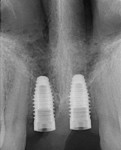

CT Guided Custom Implant Placment